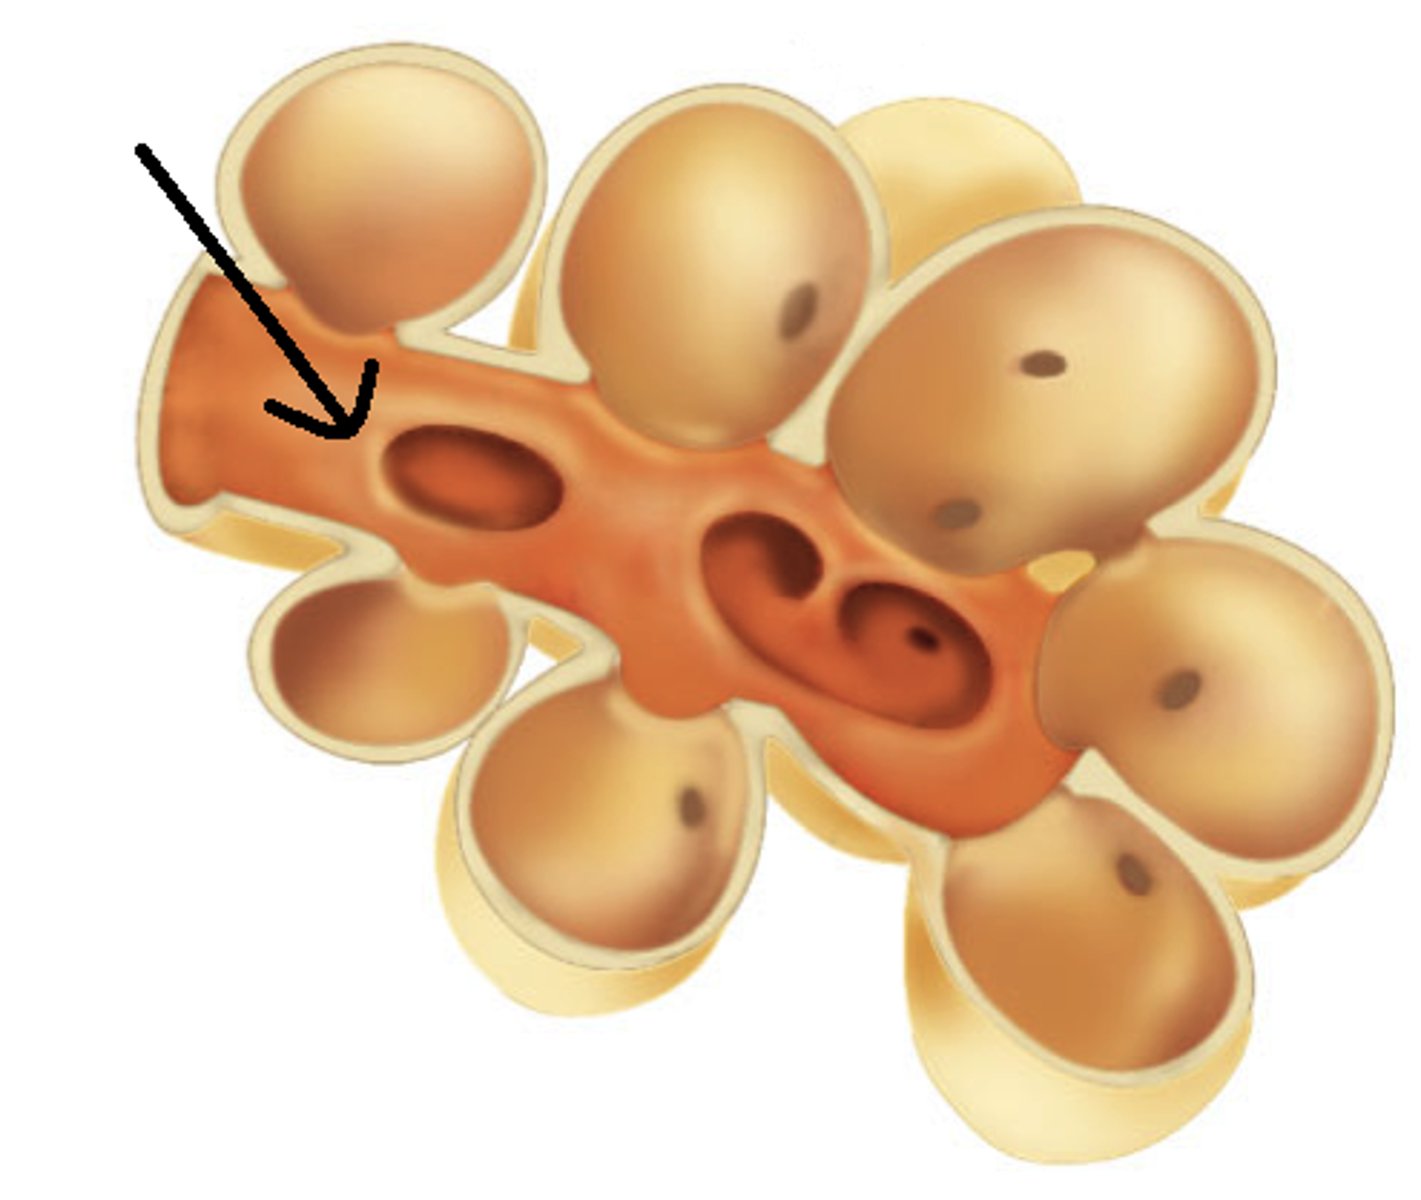

alveoli

tiny sacs of lung tissue specialized for the movement of gases between air and blood

alveolar ducts

Small passages connecting the respiratory bronchioles and the alveolar sacs.

Type I alveolar cells

simple squamous cells where gas exchange occurs

Type II alveolar cells

secrete surfactant